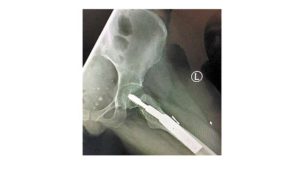

Milenia sufrió múltiples lesiones. La más seria, una fractura de cadera. El dictamen médico del perito del Instituto de Ciencias Forenses de Jalisco concluyó que Milena sufrió lesiones que pusieron en peligro su vida, que serán permanentes, y que le generaron… 60 por ciento de incapacidad.